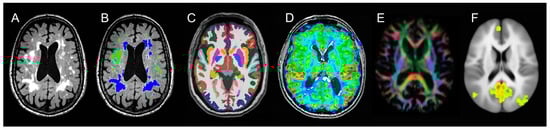

MRI data was acquired using a Siemens 3T MRI instrument with phased array RF coils and 32 channel head coils housed in the OHSU advanced imaging research center (AIRC). Subjects underwent anatomical imaging sequences similar to those used in the Alzheimer disease neuroimaging initiative [44]. Full sequence parameters are described in Table 1 and illustrated in Figure 2. Total MRI acquisition time was one hour, 10 min.

Brain MRI secondary outcomes include: (1) voxel-based morphometry (VBM) analysis using FSL software to segment GM in T1 images and calculate GM density in standard Montreal neurological institute (MNI) stereotactic space was used to examine regional differences between groups for the grey matter volumes; (2) Volumetric brain MRI using Freesurfer will be used to determine the group differences in medial temporal lobe volume changes, which is another region that may be sensitive to PUFAs [51,52,53]. The WMH masks will be used to correct the Freesurfer segmentation to provide accurate tissue type volumes because WMH appears iso-intense with GM in T1 sequences and is therefore susceptible to misclassification; (3) Diffusion tensor imaging was used to examine regional and between-group differences in white matter tracts previously linked to PUFA supplementation using TBSS [54]; (4) Pseudo-continuous arterial spin labeling (pCASL) was used to quantify cerebral blood flow and examine regional perfusion differences between groups; (5) Resting-state functional MRI examined connectivity patterns within the default mode network (Table 1 and Figure 2).

Figure 2. Neuroimaging endpoints available in the PUFA Trial. (A). Fluid-attenuated inversion recovery (FLAIR) sequence illustrating prominent total WMH; (B). WMH segmentation classified into deep (green) and periventricular (blue); (C). T1 grey matter segmentation including medial temporal lobe (brown); (D). 2D Pseudo-Continuous Arterial Spin Labeling (pCASL) sequence for cerebral blood flow; (E). Diffusion Tensor Imaging (DTI) derived fractional anisotropy direction color-coded; (F). fMRI derived default mode network activity at resting state.